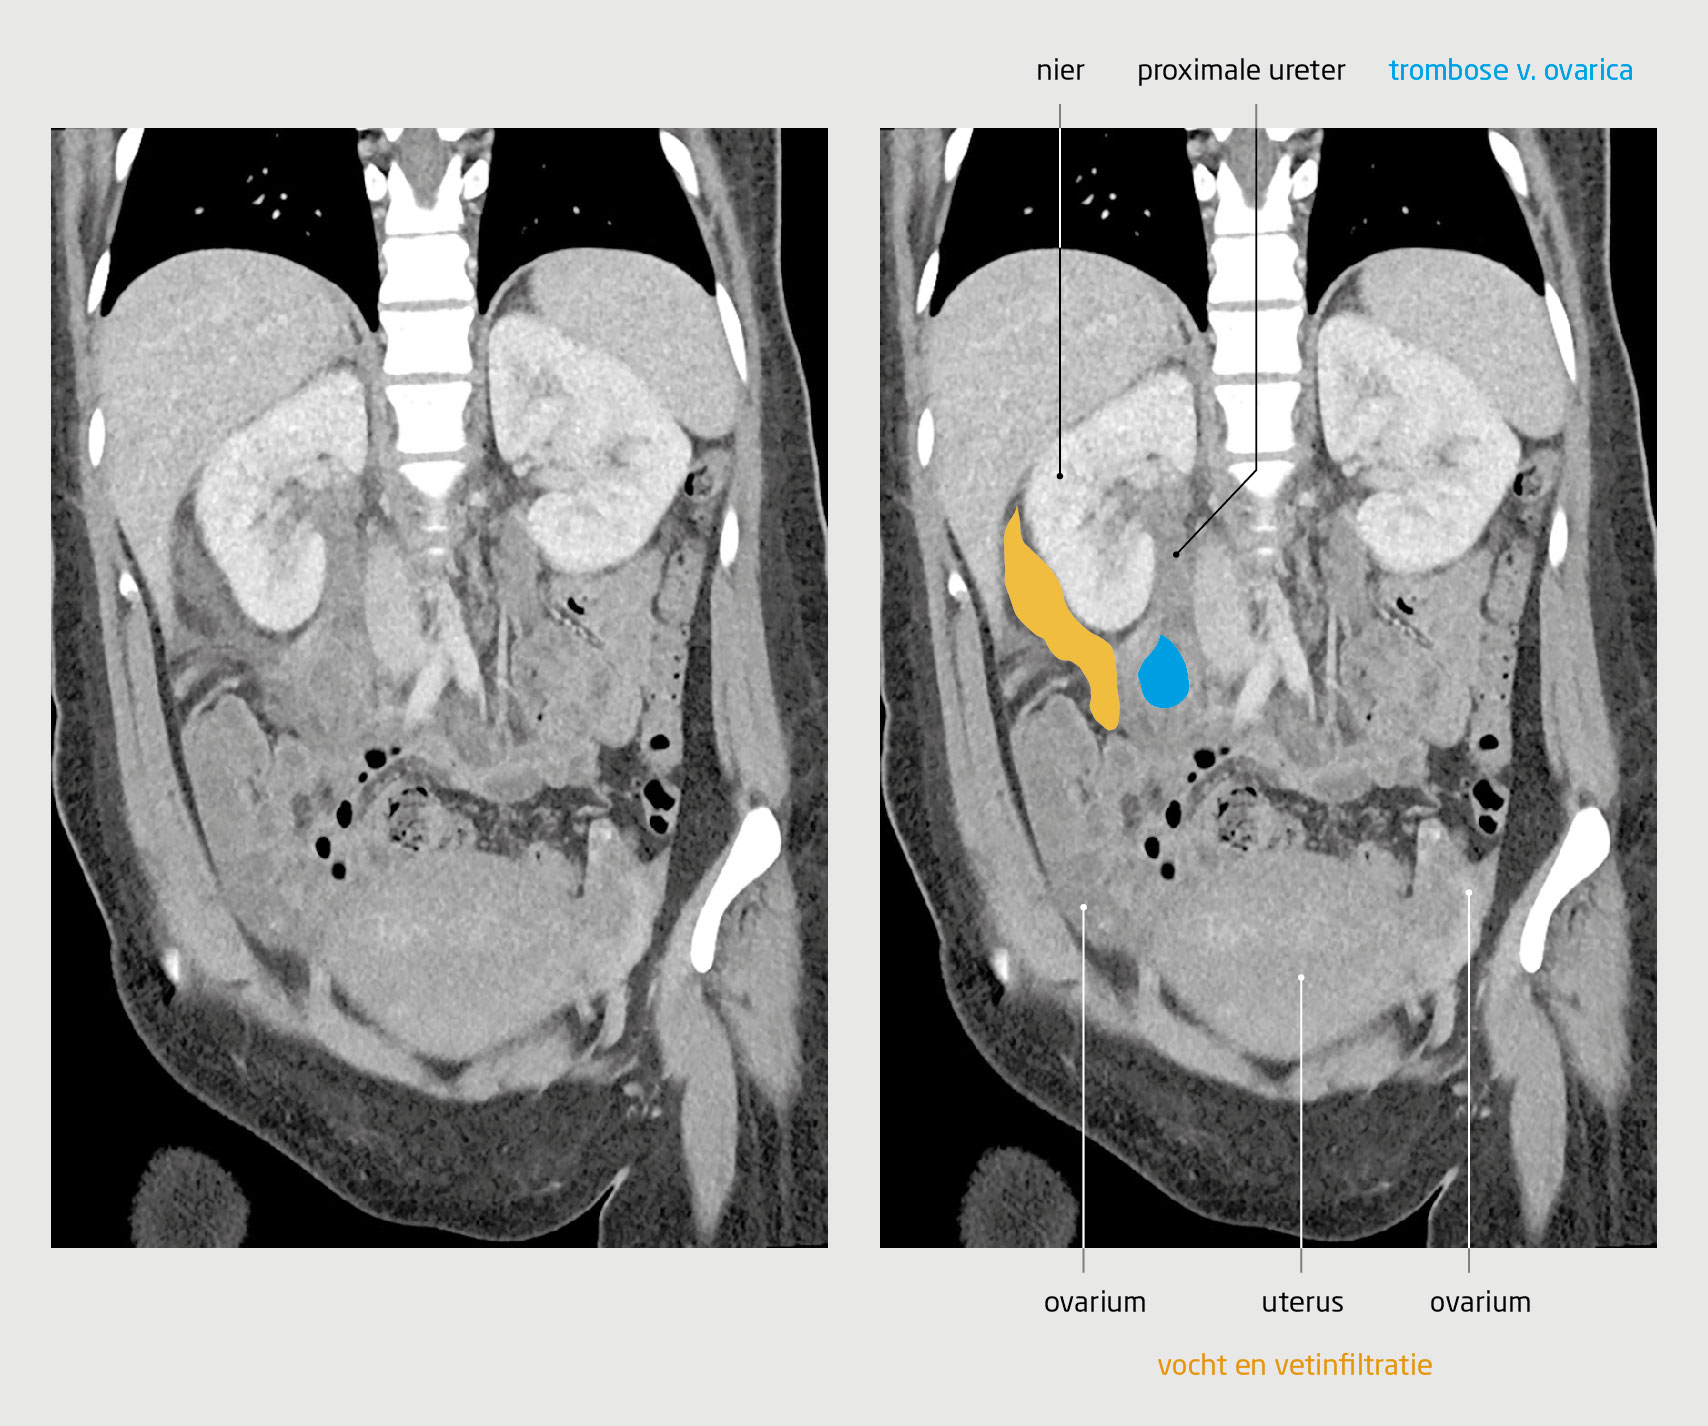

In dit stadium dachten wij aan een gastro-intestinale oorzaak van de koorts en pijn in de onderbuik, zoals een appendicitis, diverticulitis of invaginatie. De echo van het abdomen liet een hypo-echogene tubulaire structuur van 8 mm in diameter met enige vetinfiltratie zien, wat het beste paste bij appendicitis (figuur 1). De patiënte werd daarom aangemeld voor een laparoscopische appendectomie.

Echo van de rechter onderbuik van een kraamvrouw met progressieve buikpijn post partum

Figuur 1 | Echo van de rechter onderbuik van een kraamvrouw met progressieve buikpijn post partum

De echoarme tubulaire structuur met omringende vetinfiltratie op deze echo was te vervolgen van halverwege rechts in de buik tot aan de onderpool van de rechter nier. Bij compressie bleef het aspect ongewijzigd. Ter plaatse van de onderpool van de rechter nier was een spoor vocht zichtbaar.